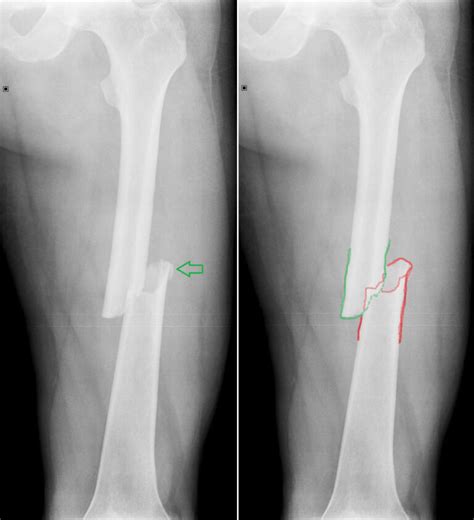

Detské zlomeniny sa líšia od zlomenín u dospelých. Detská kosť je pružnejšia a odolnejšia. Diagnostika môže byť náročnejšia, a preto sa často využíva aj porovnávacia snímka zdravej končatiny. Medzi typické detské zlomeniny patria epifyzárne zlomeniny (v oblasti rastovej chrupavky), zlomeniny z ohnutia a kompresívne zlomeniny.

Liečba detských zlomenín sa snaží byť čo najkonzervatívnejšia, často bez operácie. V prípade potreby chirurgického zákroku sa preferuje miniinvazívny prístup. Po liečbe zlomeniny je často potrebná rehabilitácia na obnovenie funkčnosti končatiny.